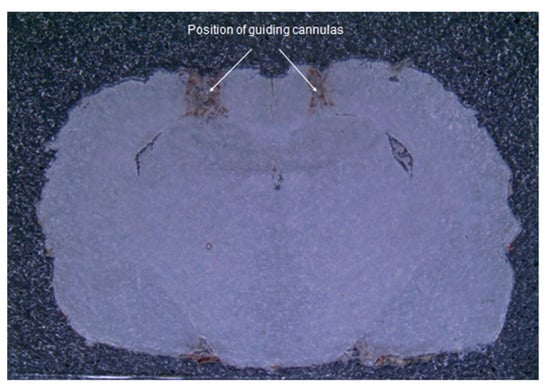

2.1. Postmortem Brain Analysis of Rats Given iHippo Injections

4.6. Postmortem Brain Analysis